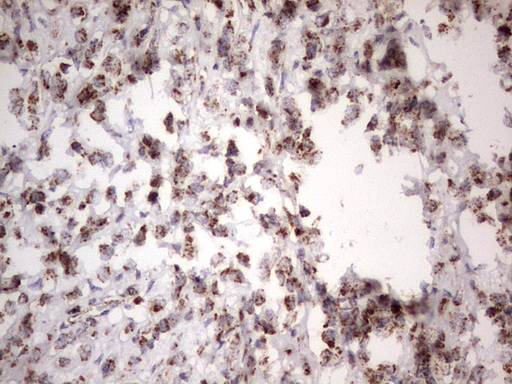

Immunohistochemical staining of paraffin-embedded Adenocarcinoma of Human breast tissue using anti-APC mouse monoclonal antibody. (M00008-2; heat-induced epitope retrieval by 1mM EDTA in 10mM Tris, pH8.5, 120°C for 3min)

Immunohistochemical staining of paraffin-embedded Adenocarcinoma of Human breast tissue using anti-APC mouse monoclonal antibody. (M00008-2; heat-induced epitope retrieval by 1mM EDTA in 10mM Tris, pH8.5, 120°C for 3min)